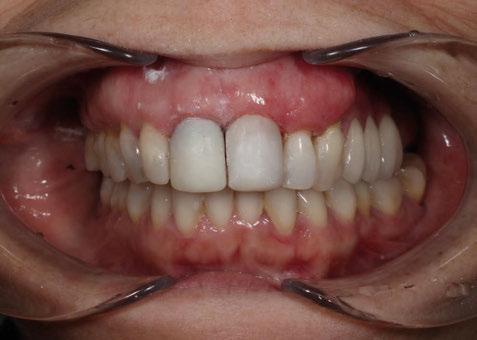

4. Fase protésica provisional

Una vez colocados los pilares provisionales de titanio, se adaptó la férula pick-up modificada y se verificó su correcto asentamiento de los pilares a través de los orificios de ésta. A continuación, se recapturó la férula a los pilares de titanio mediante resina acrílica autopolimerizable (Enamel Temp

Plus®) y, una vez polimerizada, se tomó un registro de mordida, se desatornillaron los pilares y se retiraron de boca. Seguidamente, se atornillaron los análogos verificando que no hubiera movilidad de ningún pilar y se envió al laboratorio para el acabado y pulido final, eliminando todo el soporte y añadiendo un refuerzo metálico por palatino. En boca, se colocaron los tapones de cicatrización de los transepiteliales y se le explicaron las recomendaciones postquirúrgicas y medicación necesaria. Instruimos al laboratorio a dejar los perfiles de emergencia lo más estrechos posibles y los pónticos ovoides entrando unos 3 mm en cada alveolo a fin de preservar la arquitectura gingival presente.

A las 24 horas se citó al paciente nuevamente, se atornilló el provisional en boca y se realizó una

Figura 26. Entrega del provisional de carga inmediata a las 24 horas.

ortopantomografía de verificación del ajuste pasivo de todos los implantes. Por último, tapamos las chimeneas con teflón y resina provisional y se chequeó nuevamente la oclusión, dando nuevamente las instrucciones de higiene y mantenimiento de la prótesis provisional (Figuras 24-27).